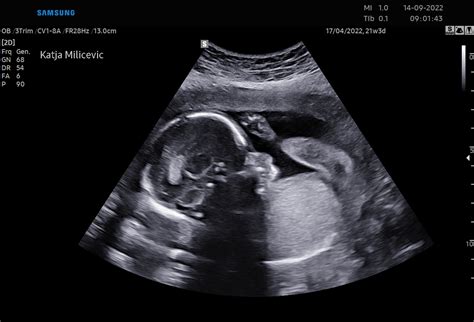

Drugi ultrazvočni pregled, znan kot morfološki pregled, se izvede med 19. in 23. tednom nosečnosti (nekateri viri navajajo med 20. in 24. tednom). Ta poglobljeni pregled omogoča oceno ustreznosti plodovega razvoja, prepoznavanje morebitnih nepravilnosti v razvoju in rasti ploda, oceno količine plodovnice ter pregled strukture in lege posteljice. V času tega pregleda se natančno preverijo vsi organi ploda, vključno z glavo, možgani, hrbtenico, srcem, želodcem, ledvicami, mehurjem, okončinami in prsti na rokah in nogah. Ginekolog pri tem išče morebitne "mehke" ali "trde" označevalce, ki bi lahko nakazovali na kromosomske napake.